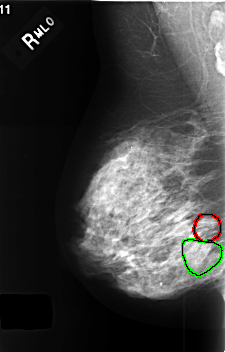

C_0407_1.RIGHT_MLO

FILE: C_0407_1.RIGHT_MLO.OVERLAY

TOTAL_ABNORMALITIES 2

ABNORMALITY 1

LESION_TYPE CALCIFICATION TYPE AMORPHOUS DISTRIBUTION CLUSTERED

ASSESSMENT 4

SUBTLETY 3

PATHOLOGY BENIGN

TOTAL_OUTLINES 1

BOUNDARY

ABNORMALITY 2

LESION_TYPE CALCIFICATION TYPE PLEOMORPHIC DISTRIBUTION SEGMENTAL

ASSESSMENT 3